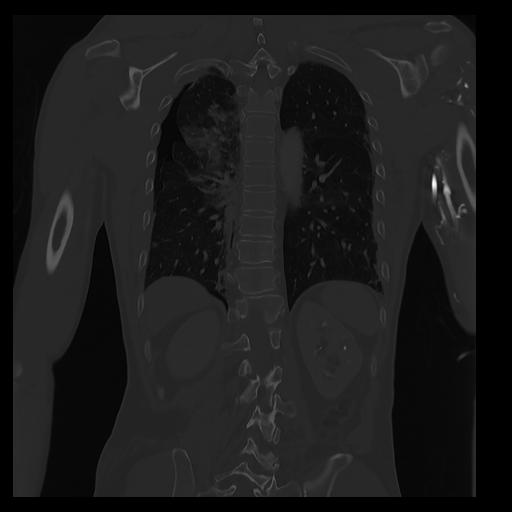

32 PULMON,CE,Coronal,3.000,PULMON,Coronal,